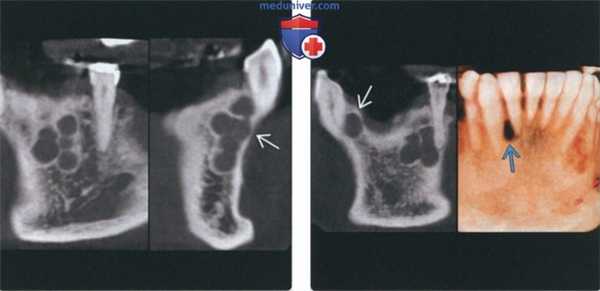

(Слева) На корональной КЛКТ (слева) у этого же пациента определяются небольшие округлые рентгенонегативные участки, хорошо отграниченные кортикальной пластинкой. На КЛКТ (профильный срез) справа определяется истончение щечной кортикальной пластинки в отсутствие вздутия. Эти признаки могут быть полезны при дифференциальной диагностике с амелобластомой.

(Справа) На корональной КЛКТ (слева) у этого же пациента определяется еще одно однокамерное образование в передних отделах нижней челюсти справа. На 3D КЛКТ (справа) определяется типичная боковая периодонтальная киста в виде «слезы» между корнями зубов.

(Слева) При сагиттальной КТ в коаном окне в области апикального отверстия корня первого премоляра нижней челюсти справа визуализируется однокамерная киста, хорошо отграниченная от окружающих тканей кортикальной пластинкой. Киста тесно прилежит к твердой пластинке и пространаву периодонтальной связки, что свидетельствует о ее воспалительной природе.

(Справа) При сагиттальной КТ в костном окне в верхней челюсти визуализируется периапикальная киста среднего размера, целостность ее верхней стенки на ограниченном участке нарушена. Определяются также признаки ассоциированного с кистой верхнечелюстного синусита одонтогенного характера.